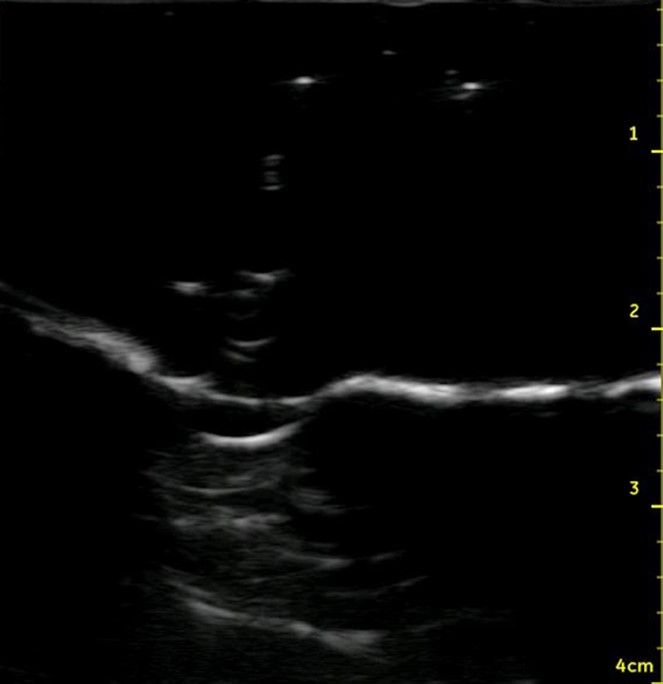

Figure 1.Ultrasound of the midsagittal plane of the anterior neck showing the thyroid cartilage (T.C.), cricothyroid membrane (C.T.M.), cricoid cartilage (C.C.), and the first tracheal ring (T.R.).

Figure 6. Midsagittal ultrasound of the anterior neck of a live person

Figure 7. Midsagittal ultrasound of the anterior neck of the model